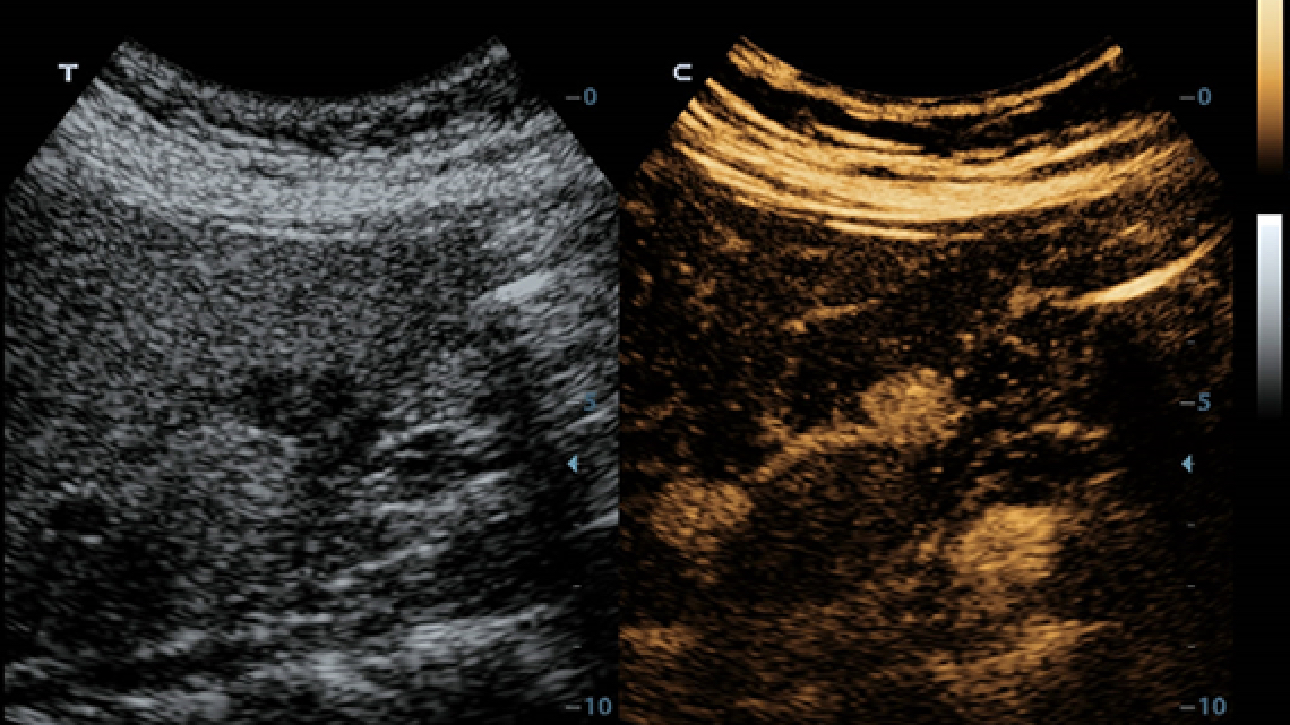

X-Insight is een inzichtelijke oplossing om meer visie te krijgen.

De gloednieuwe oplossing van Mindray is het geslaagde product dat is voortgekomen uit voortdurende klantinzichten in klinische behoeften in combinatie met steeds evoluerende, geavanceerde ultrasoundtechnologie?n. Vol energie en gebrand op toekomstgerichte inzichten en eindeloze mogelijkheden: dankzij de verhoogde schaalbaarheid wordt de oplossing continu verbeterd.

Als allround partner zet DC-60 Exp met X-Insight zich in om een allesomvattende oplossing te zoeken waarmee u alle aspecten van uw dagelijkse klinische activiteiten gemakkelijk en trefzeker kunt beheren.

De DC-60 Exp met X-Insight is ontworpen op basis van diepgaand inzicht in klantbehoeften om hoge effici?ntie met nauwkeurige beeldverwerking te leveren, dankzij eXacte helderheid, eXceptionele intelligentie en eXcellente ervaring.

eXcellente ervaring

Uiterst productieve ervaring